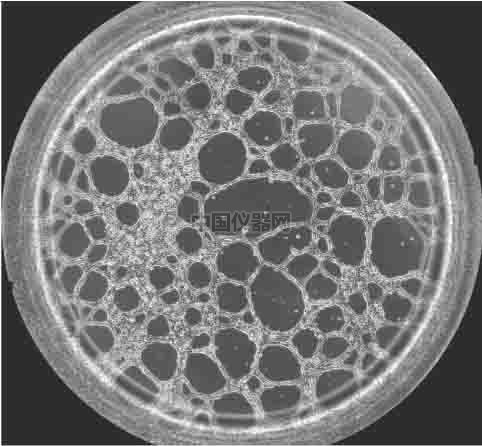

圖一 血管生成鏡檢圖 一.實(shí)驗(yàn)材料和實(shí)驗(yàn)方法 1.實(shí)驗(yàn)材料

前言 無(wú)論原發(fā)性腫瘤還是繼發(fā)性腫瘤,一旦生長(zhǎng)直徑超過(guò)1~2 mm,都會(huì)有血管生成。這是由于腫瘤細(xì)胞自身可分泌多種生長(zhǎng)因子,誘導(dǎo)血管生成。多數(shù)惡性腫瘤的血管生成密集且生長(zhǎng)迅速。因此,血管生成在腫瘤的發(fā)展轉(zhuǎn)移過(guò)程中起到重要作用,這一過(guò)程將能明顯阻止腫瘤組織的發(fā)展和擴(kuò)散轉(zhuǎn)移。于是體外的血管生成實(shí)驗(yàn)就能很好的模擬腫瘤的血管發(fā)生過(guò)程,并且適合研究藥物對(duì)這一過(guò)程的影響實(shí)驗(yàn)。本實(shí)驗(yàn)以HUVEC細(xì)胞為例,介紹這一實(shí)驗(yàn)的詳細(xì)過(guò)程。